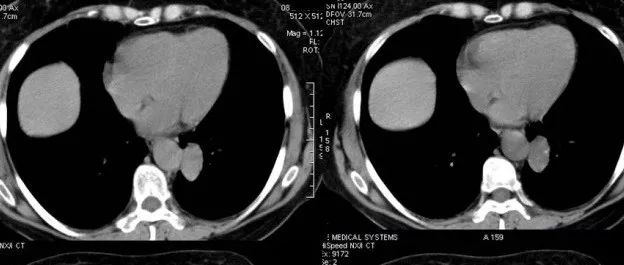

医学影像  yxyx-app  医学影像APP,打造伴随医生快速成长的影像学习社区。与影像园(Xctmr.com)一起提供最全面的影像案例库、基础(解剖、病理、影像诊断)知识、影像技术及考题等,为医生提供最佳的医学影像参考。【所属科室】呼吸科【基本资料】患者,女,58岁【主诉】间断咳嗽1月余【影像图片】【讨论问题】如何诊断?【医学影像APP用户讨论】评论:左肺下叶后基底段见类椭圆形软组织肿块影,边界清,未见明显分叶及毛刺,内密度欠均匀,可见点状高密度钙化灶。邻近左肺下叶后基底段支气管管腔通畅,病变与内侧胸主动脉间脂肪间隙存在。增强扫描,病变动脉期呈轻度强化,延迟扫描,病变呈渐进性强化,其密度与邻近腹主动脉密度接近。左侧胸腔内未见积液征。左肺下叶良性病变,硬化性血管瘤可能性大。...